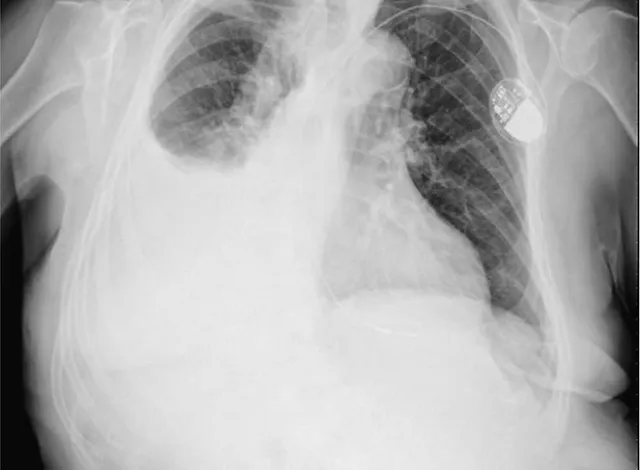

La evaluación por imágenes, particularmente a través de la radiografía de tórax, proporciona evidencia visual clave para el diagnóstico del derrame pleural. En una radiografía, el derrame se manifiesta como una opacidad en el área del pulmón, con un nivel horizontal de líquido visible en proyecciones de pie o una opacidad en la base del pulmón en proyecciones acostadas. Los signos radiográficos adicionales, como el desplazamiento del mediastino o la ampliación de la silueta cardiaca, pueden indicar la presencia de un derrame grande.